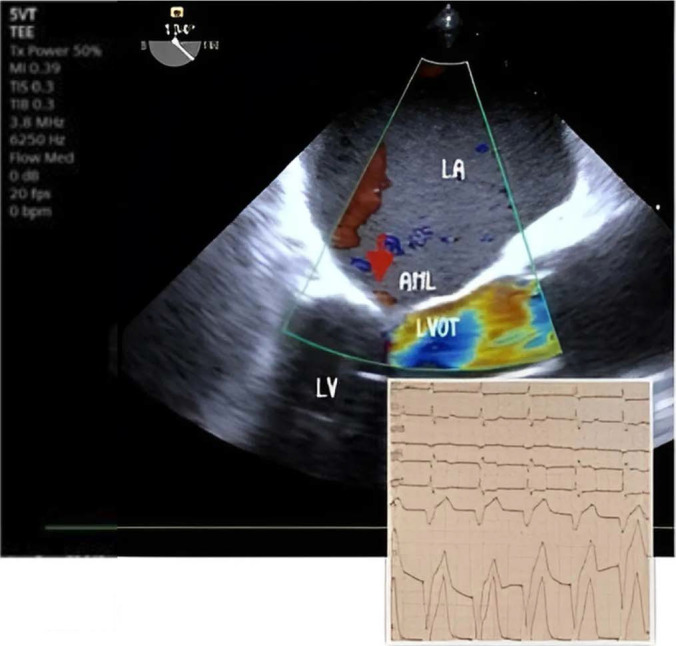

Systolic anterior motion (SAM) of the mitral valve refers to the unusual movement of the anterior and sometimes the posterior mitral valve leaflets toward the left ventricular outflow tract (LVOT) during systole. This phenomenon is most frequently associated with the asymmetric septal variant of hypertrophic cardiomyopathy (HCM), but it can also occur in conditions like acute myocardial infarction, diabetes mellitus, hypertensive heart disease, after mitral valve repair, and even in asymptomatic individuals during dobutamine stress tests. We present a case of transient SAM induced by a junctional rhythm along with high doses of dobutamine and nitroglycerin in an intensive care unit (ICU) setting. Transesophageal echocardiography (TEE) played a crucial role in detecting SAM and showed that transitioning from a junctional rhythm to a ventricular paced rhythm led to an improvement in the SAM condition.

Abstract Image